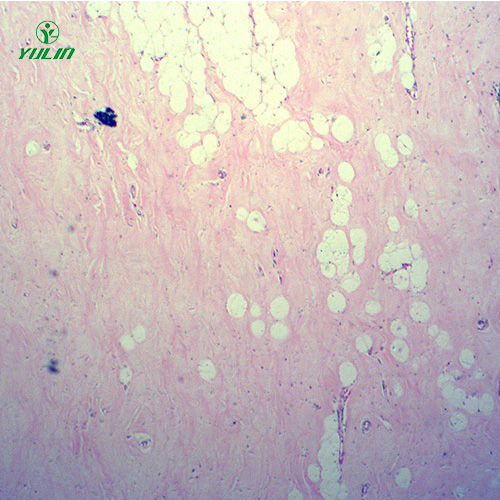

湖南炎症病理玻片

产品内容说明 /Product description

人体病理切片,炎症病理玻片,炎症病理玻片价格